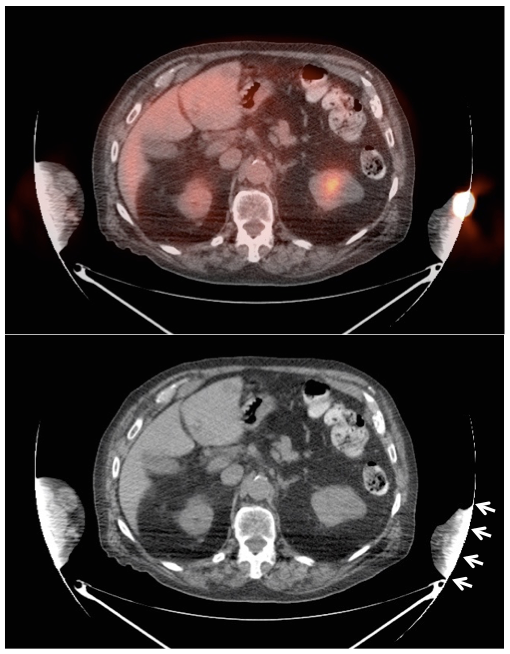

If the volume of extravasation is large enough, it can result in a significant reduction of circulating FDG available for tumoral uptake, resulting in false negative results (“Sponge Effect”, discussed here).